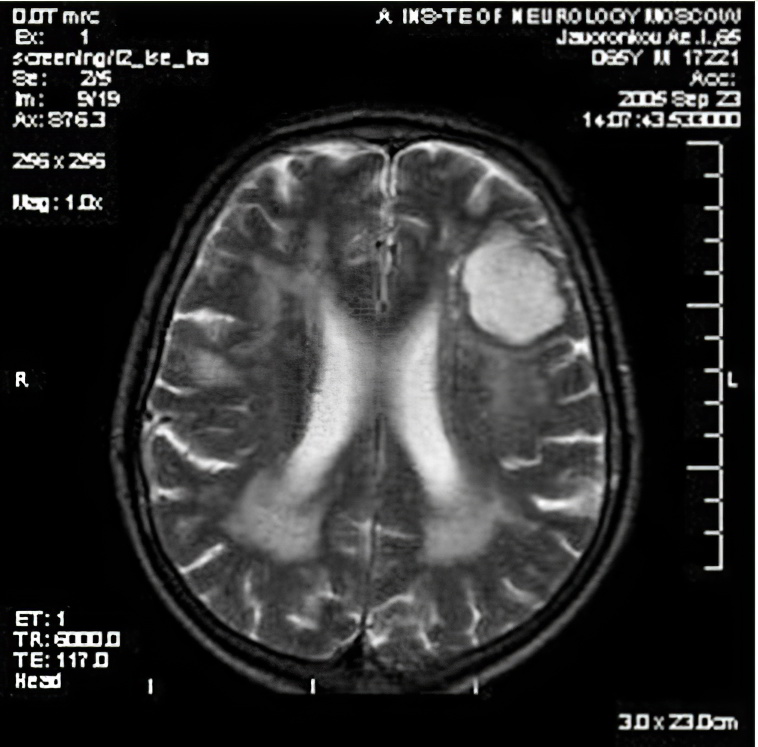

Диагностика заболеваний нервной системы начинается с неврологического осмотра пациента. В ходе обследования оцениваются сознание, интеллект, ориентация во времени и пространстве, чувствительность, рефлексы и другие параметры. Иногда заболевание можно определить по клиническим признакам, но чаще для постановки диагноза требуются дополнительные исследования.

К ним относится компьютерная томография головного мозга, которая выявляет новообразования, кровоизлияния и другие патологические изменения. Более детальную информацию предоставляет магнитно-резонансная томография (МРТ). Для диагностики сосудистых нарушений применяются ангиография и ультразвуковое исследование.

Также могут использоваться люмбальная пункция, рентгенография и электроэнцефалография. Среди других методов исследования выделяются биопсия, анализ крови и ряд других процедур.